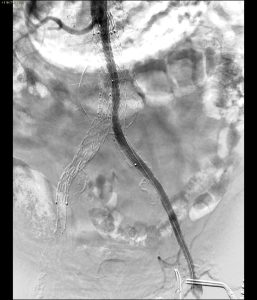

- Controllo finale con ottimo risultato angiografico

Il risultato finale dell’intervento è stato ottimale:

- Pervietà completa di entrambe le arterie renali.

- Flusso sanguigno eccellente attraverso lo stent Viabahn.